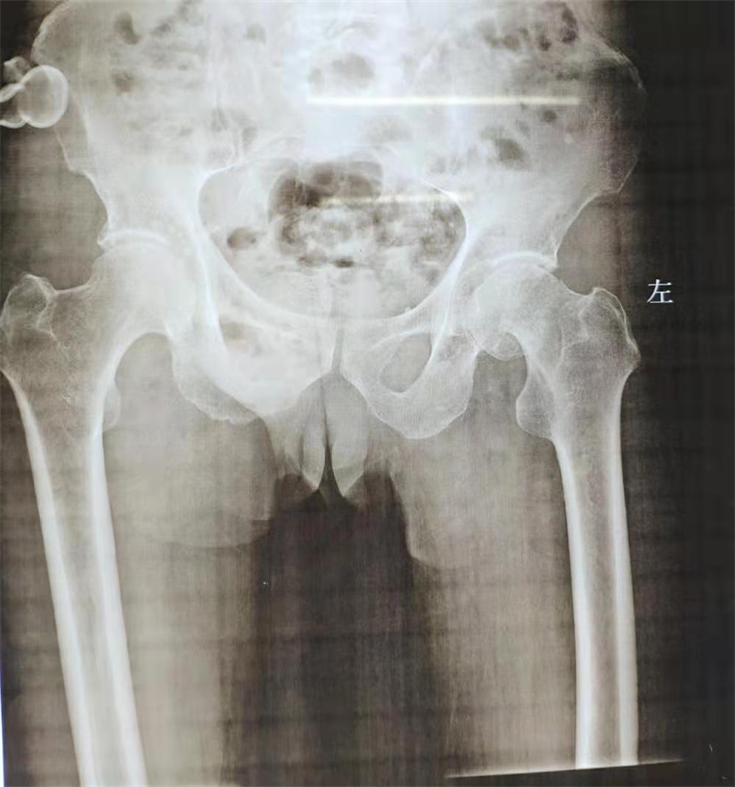

11月初,一位特殊的患者慕名找到张勤安主任医疗团队,希望张主任团队能帮助他恢复健康,经查,该患者男,77岁,摔伤致左髋部疼痛7天;既往有急性脑梗病史,现遗留左侧肢体活动障碍,查体发现左上肢肌力1-2级,左下肢肌力2-3级,臀中肌肌力2-3级,X片显示左侧股骨颈头下型骨折。

患者术前影像学资料

该患者具有全髋关节置换的适应症,但因下肢肌力较弱,尤其是臀中肌肌力薄弱,术后假体脱位风险较高。所以张勤安主任经过认真研究,再三确认,考虑到患者年龄和活动康复需求,在与患者家属充分沟通后,张勤安主任医疗团队决定为患者实施双动全髋关节置换手术。